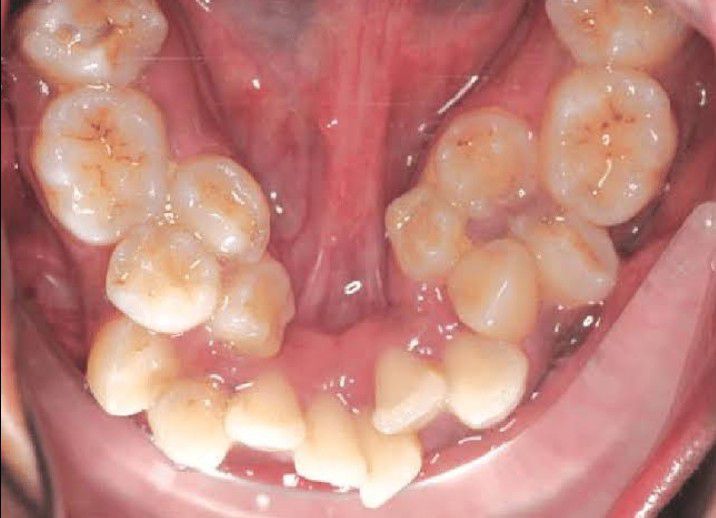

Supernumerary teeth (ST) are odontostomatologic anomaly characterized by as the existence excessive number of teeth in relation to the normal dental formula. This condition is commonly seen with several congenital genetic disorders such as Gardner's syndrome, cleidocranial dysostosis and cleft lip and palate.